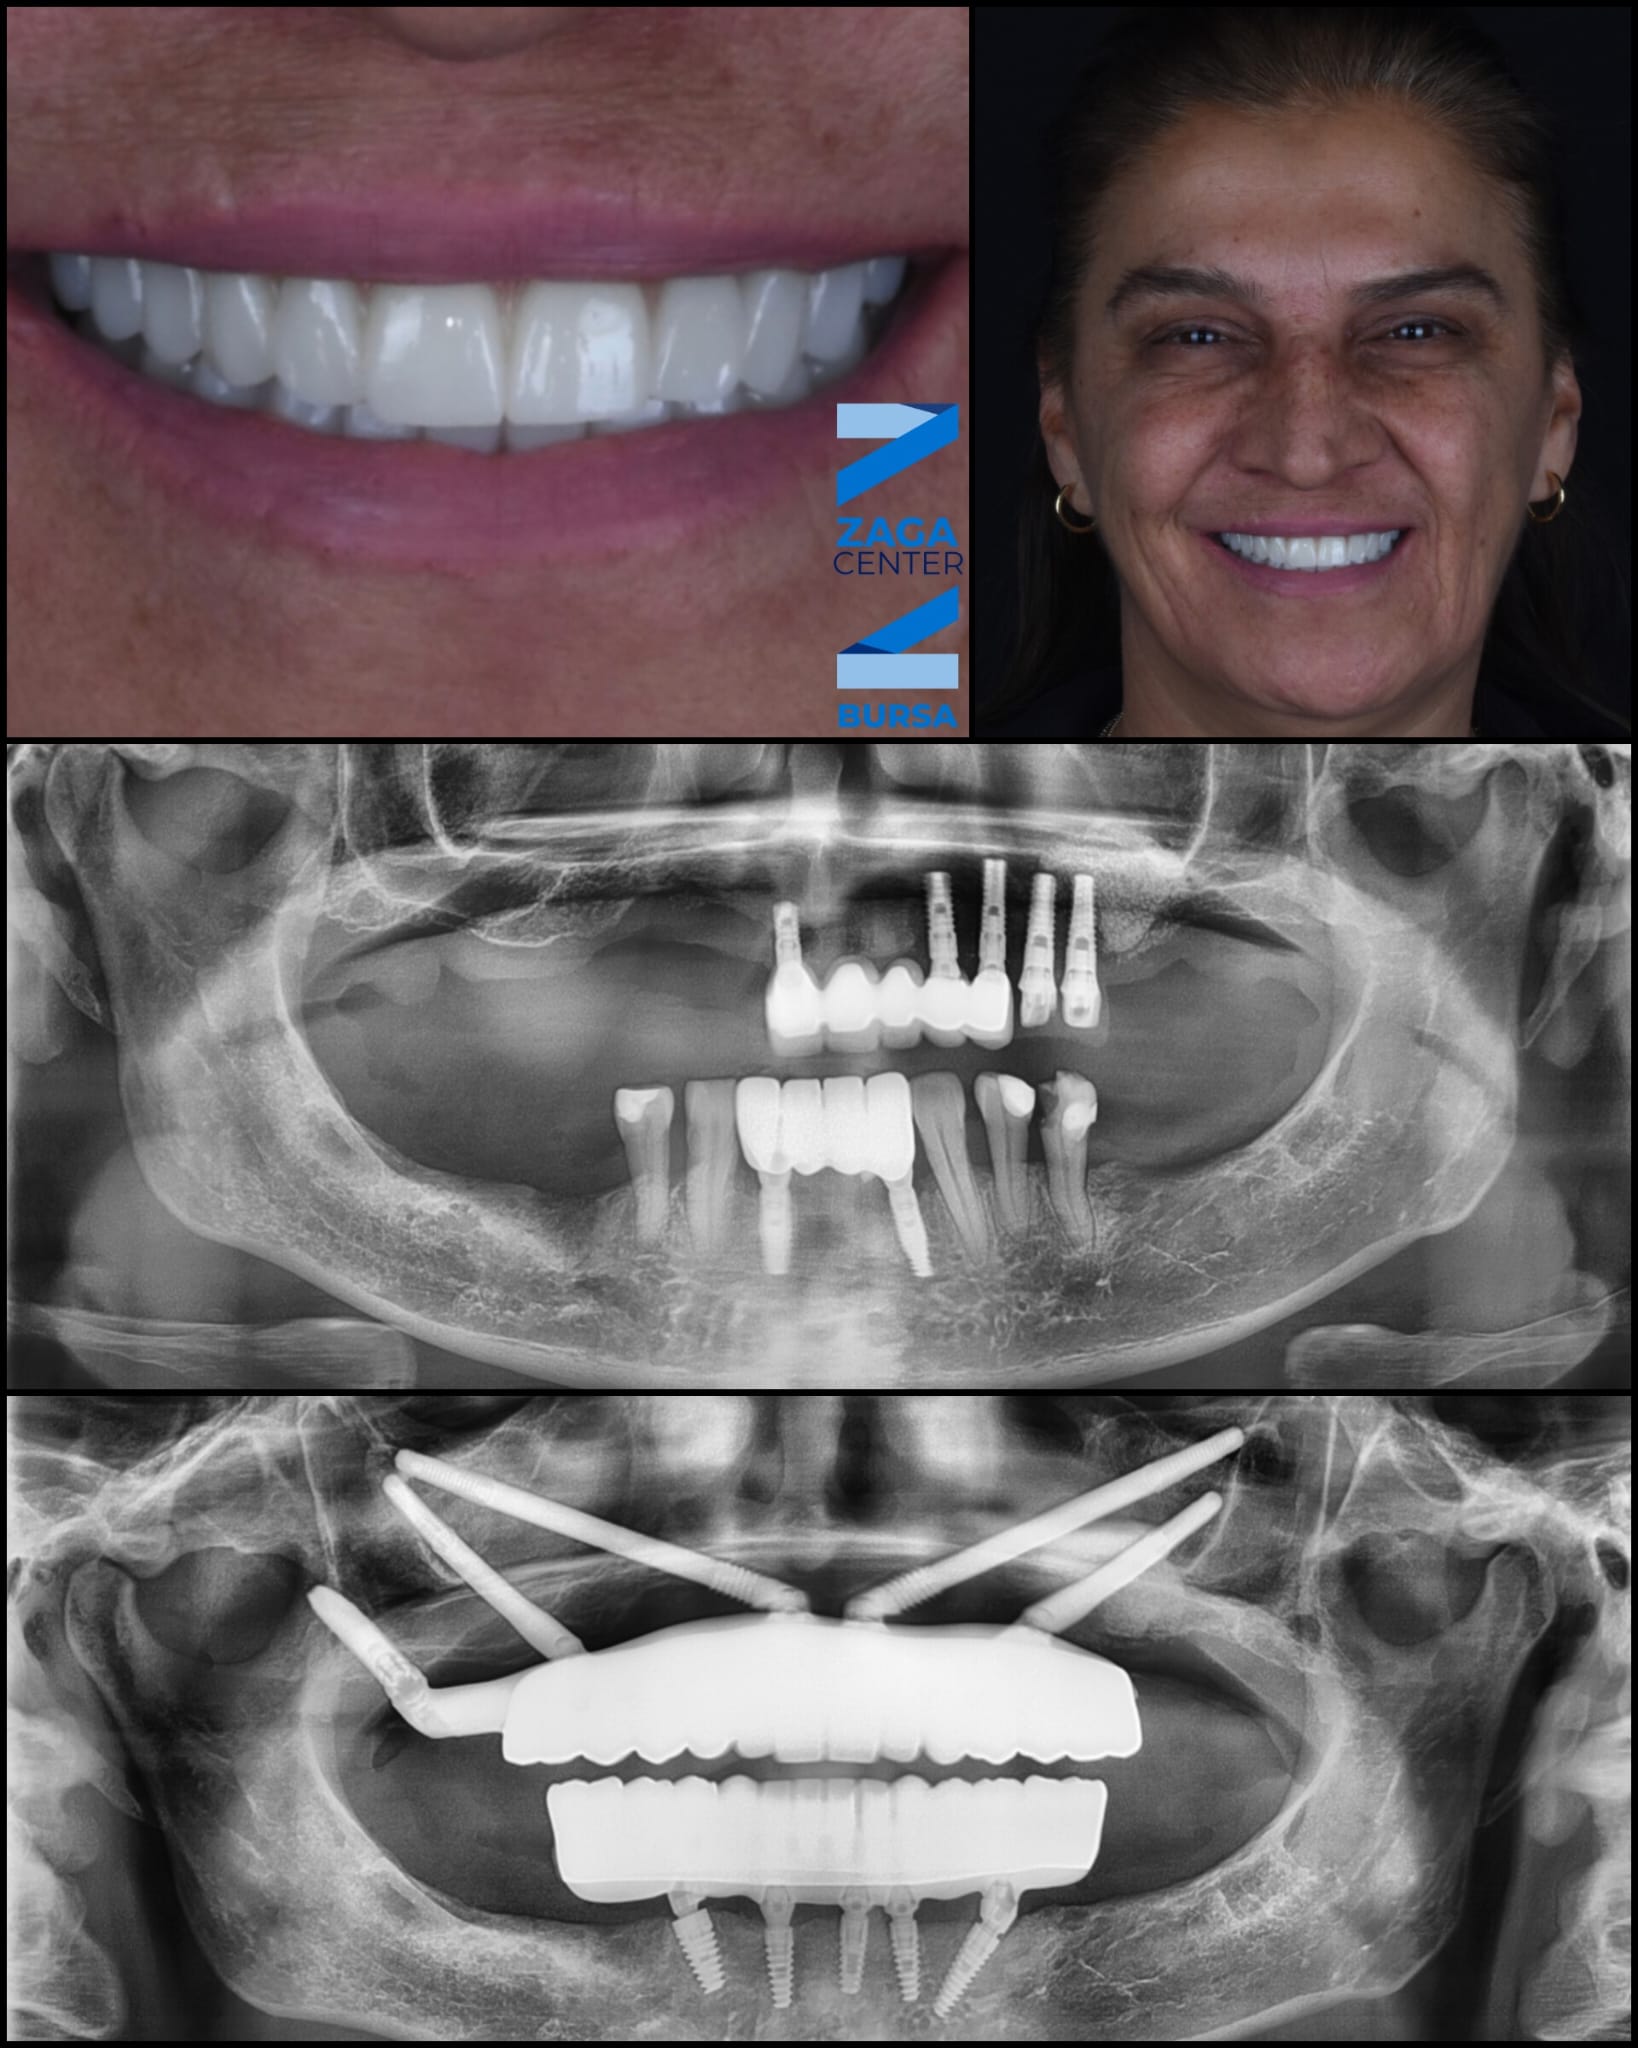

Patient Transformations

See the life-changing results of the ZAGA Philosophy.

Full Arch Restoration

Before

Before treatment

After

After treatment

Immediate Loading Success